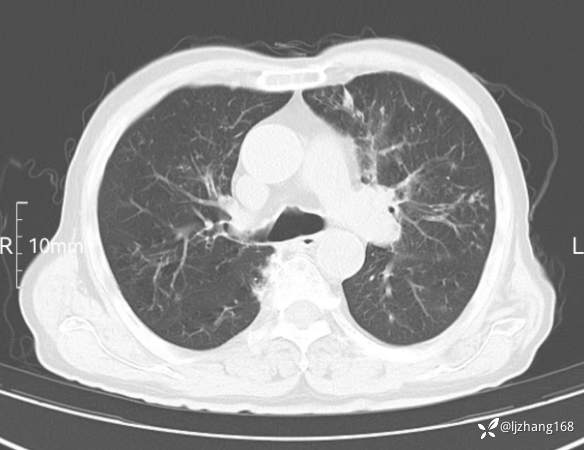

老年男患,咳嗽,气短,双肺多发间质性病变,何种感染?(有结果)

辅助检查:胸部CT:双肺肺气肿,间质性病变,血气分析:PH 7.413, PCO2 29.2mmHg, PO2,81.8mmHg,乳酸 3.3mmol/1,剩余碱-4.0mmol/1,HC03 18.8mmol/1。全血超敏C反应蛋白:超敏C反应蛋白 135.60 mg/L、 白细胞 14x19^9/L,中性粒细胞11.6x10^9/L。